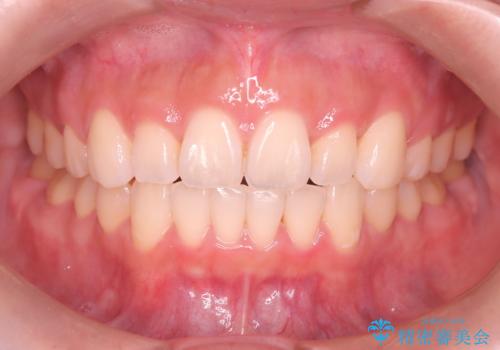

治療開始前に、下顎位の評価をおこなうことで、完成度の高い治療を行うことができました。